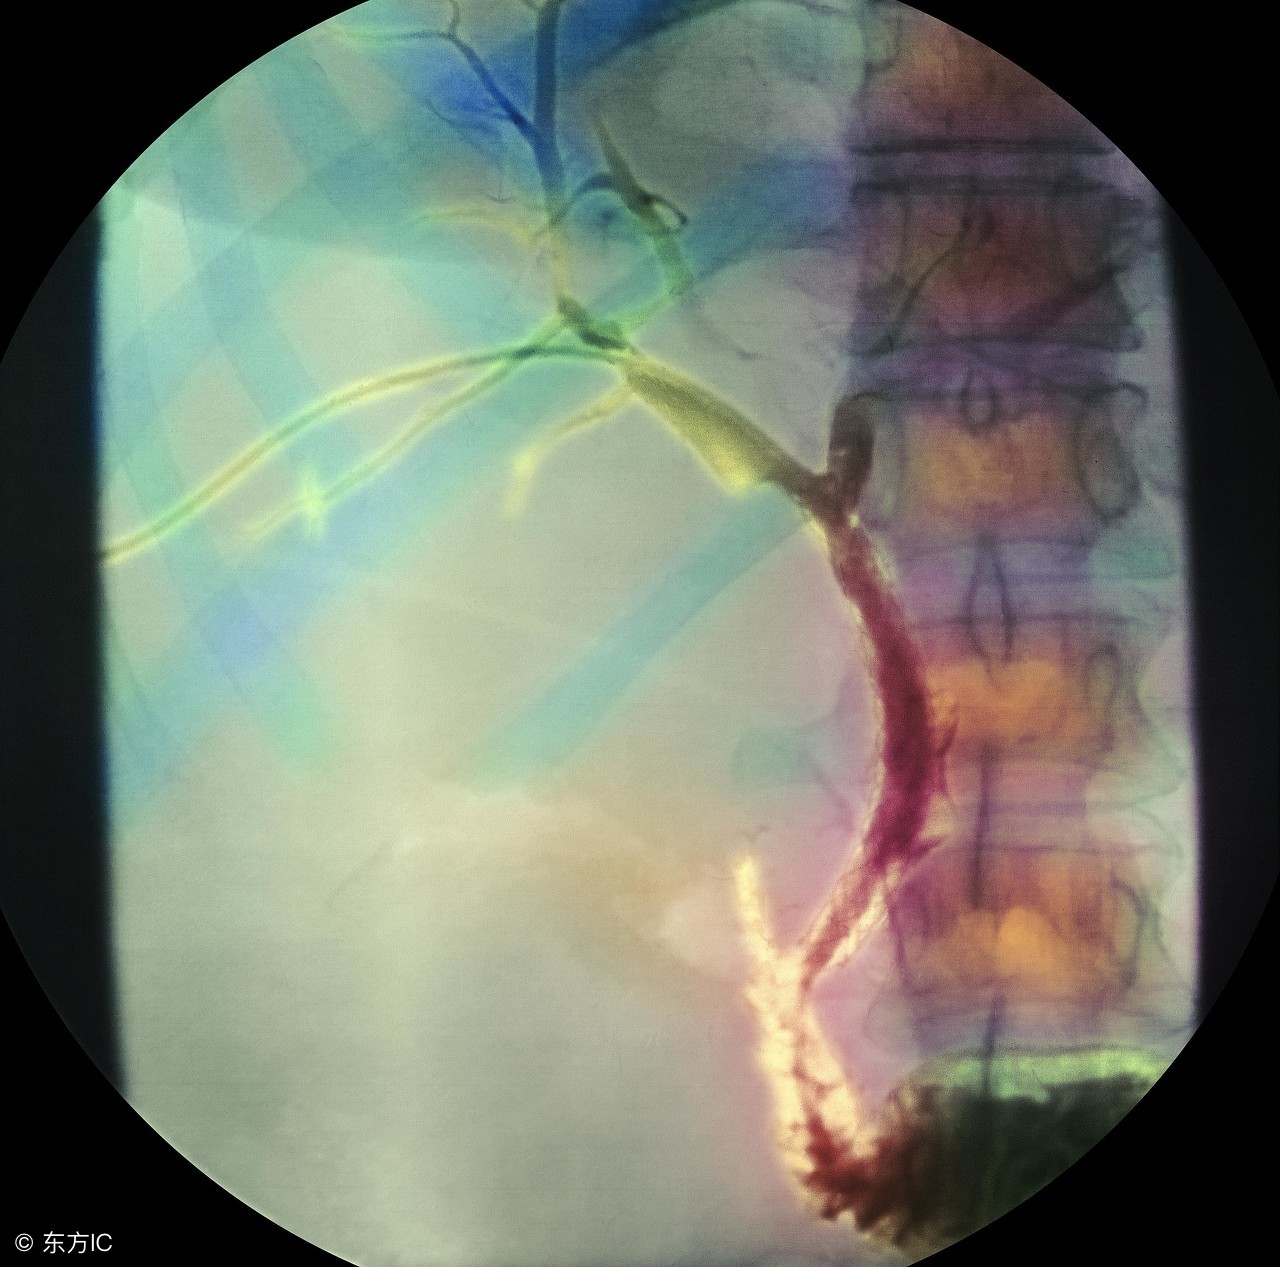

胆管癌的治疗。胆管癌可以通过手术治疗、放射治疗和化学治疗等方法治疗。对于胆管癌的治疗,首先早期以手术切除为主,手术后可以放疗或化疗配合治疗,以巩固手术治疗的效果。对于胆管癌晚期患者来说,可以通过胆道引流手术改善患者肝脏功能,减少并发症的出现,延长患者生命。放射治疗只是一种辅助性治疗,一定程度上提高了患者的生存率。化学治疗对胆管癌来说并没有明显的治疗作用,但是化疗也可以有效的缓解胆管癌所引起的并发症,延长患者的存活期,也不失为一个有效的辅助治疗方法。